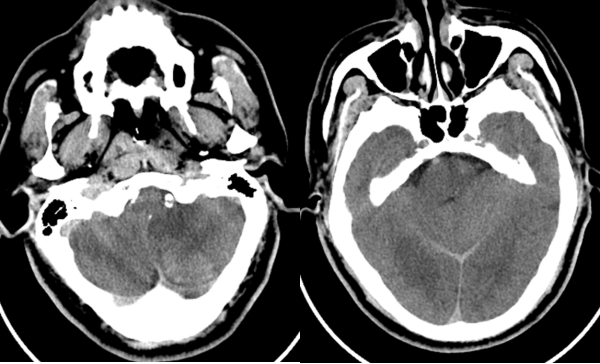

六十多岁的朱先生因“头晕19小时意识不清2小时”来到我院急诊,急诊神经科医师接诊后考虑脑血管疾病,立即行头颈部CTA+CTP检查,判断闭塞血管及梗死面积。影像科张卫国主任团体第一时间完成头颈CTA+CTP后处理,结果提示患者左侧椎动脉V1段起始处次全闭塞,右侧椎动脉V4段闭塞;基底动脉闭塞;双侧椎动脉供血区(双侧小脑、脑干、部分颞叶)缺血性灌注异常。

由于患者错过了4.5小时脑卒中静脉溶栓救治时间,无法溶栓治疗。郝永岗副主任带领神经血管介入团队评估病情后决定在全麻下为患者实施动脉取栓术,挽救处在缺血状态尚未坏死的脑组织。麻醉科李健主任第一时间到达导管室,保障手术顺利进行,术中可见患者基底动脉末端闭塞(基底动脉尖综合征)。医生运用SWIM技术取出黑红色血栓,复查造影显示:基底动脉远端血流通畅,双侧大脑后动脉、小脑上动脉显影。术中发现患者左侧椎动脉起始部重度狭窄,于病变处植入支架一枚,血管狭窄解除,术后送重症医学科继续治疗。